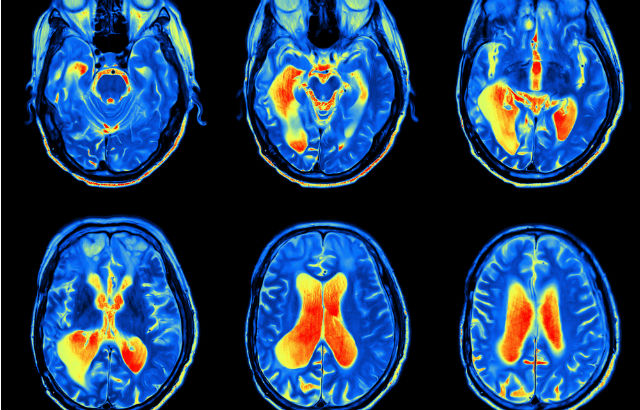

Around 145,000 people in the UK are diagnosed with Parkinson's disease - a condition in which parts of the brain become progressively damaged over many years, leading to involuntary shaking (tremor), muscle stiffness and slow movement, among other symptoms.